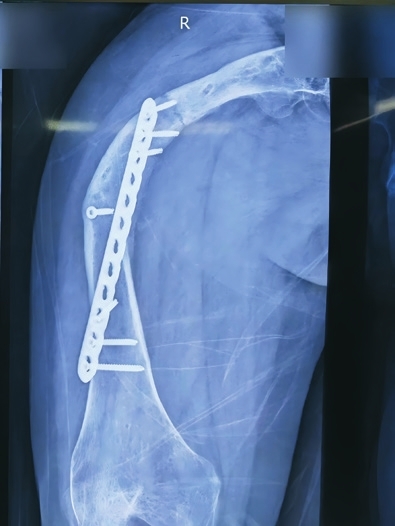

原来,张女士从小就患上了一种怪病,这导致她本身的骨头质量很差,骨头的强度也不够,右侧大腿严重向外弯曲。祸不单行的是,2021年,张女士不慎发生了车祸,她的右侧大腿股骨干被撞骨折。当时张女士采用了传统钢板内固定方法进行治疗。随着时间的推移,张女士骨头逐渐痊愈。谁料就在今年2月,张女士又再次发生车祸,仍然是右侧大腿股骨发生了骨折,这使得张女士被迫再次接受手术,腿骨又一次用钢板固定起来。经过一段时间的休养,张女士重新恢复了自主行走。然而,今年7月,命运似乎又和张女士开起了玩笑。有一天,张女士在家不经意地从座椅上站起时,只听见“嘎巴”